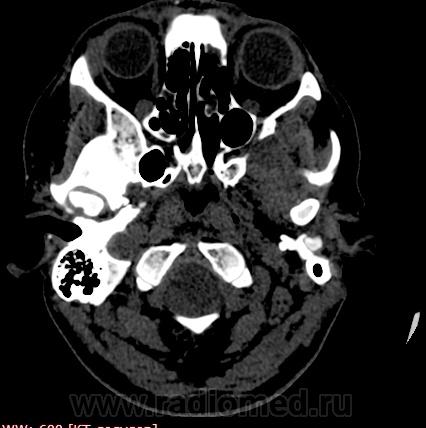

Прошу разрешить спор. По КТ - норма. Женщина, 1967г.р., жалобы на головную боль, больше в затылочной области. По-моему, не КТ-шное это дело но всеж...

Открыл. В мозгу ничего осбенного не увидел. По поводу Киари ничего не скажу, на аксиалах не вижу, а реконструкции эти срезы не строят Да и отношусь я к этой патологиии как к норме.

Аномалию Арнольда-Киари 1типа.

На МРТ выставили  аномалию Арнольда-Киари 1, нам сказали фу... На что я ответил, что по " ловцу и рыба". Во - первых, линию на КТ провести сложно ( в данном иссл.), во-вторых - естественные артефакты костей основания. И вообще пошли на...МРТ! Но осадок остался.

Для Арнольда-Киари I МРТ - как раз и есть метод диагностики, а на КТ это дело можно лишь заподозрить. Плюньте на осадок. Ну хотите, я плюну?) Тока отойдите, а то разъест))).